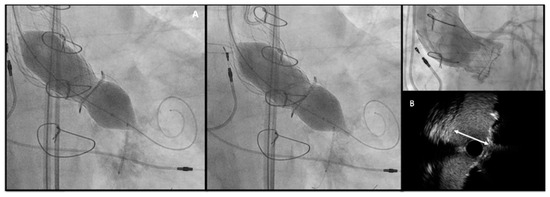

- Chimney snorkel stenting technique: Wiring the coronary artery and putting a stent on standby to be eventually implanted after THV deployment if the coronary flow is inadequate at angiographic control (Figure 7);

Figure 7. Double Chimney Stenting Technique with 4.0 × 33 Everolimus eluting stent implantation at ostial RCA and 4.0 × 18 at proximal left main before Corevalve Evolut Pro + 23 mm valve-in-valve implantation in a Mitroflow 23. - -